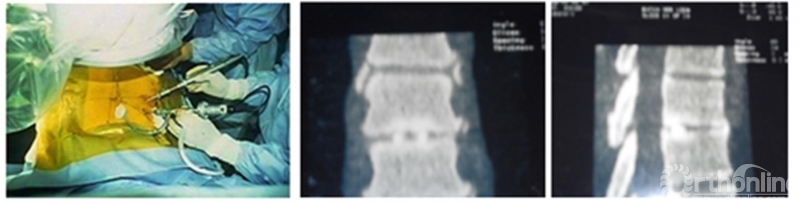

Osman在随后的12年里一直持续定期进行单侧双通道脊柱内镜手术。除此之外,他也同时涉猎小切口显微镜技术和单通道脊柱内镜技术,但是Osman敏锐的提出:单侧双通道脊柱内镜技术中操作器械可以独立于镜头并可以使用更大的手术器械(如环钻、刮勺、磨钻、刨刀等)(The purpose of using this approach is to facilitate maneuverability of the instruments independent of the arthroscope, as well as to accommodate larger instruments, such as shavers, burs, curettes, and trephines to remove hard discs.),认为这些优点便是双通道脊柱内镜相较于单通道脊柱内镜的一种创新[18]。可以认为,DE Antoni和Osman是现代UBE/BESS技术重要的的奠基者。

图5. Osman的单侧双通道内镜手术图及自体骨融合。引自Osman SG, Schwartz JA, Marsolais EB. Arthroscopic discectomy and interbody fusion of the thoracic spine: A report of ipsilateral 2-portal approach. Int J Spine Surg 2012; 6:103-109.